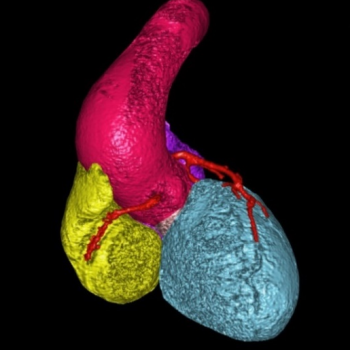

Centrum komplexní péče o vrozené srdeční vady v dospělosti vzniklo  v roce 2015  díky spolupráci  Centra kardiovaskulární a transplantační chirurgie s Interní kardiologickou klinikou Fakultní nemocnice  Brno a nabízí zcela komplexní péči o dospělé nemocné s vrozenou srdeční vadou. Portfolia jednotlivých pracovišť se navzájem doplňují.  Centrum poskytuje ambulantní sledování pacientů se všemi typy vrozených srdečních vad, neinvazivní a invazivní diagnostiku včetně transesofageální echokardiografie s využitím 3D zobrazení.  Centrum kardiovaskulární a transplantační chirurgie Brno provádí operace, reoperace a  intervenční výkony u vrozených srdečních vad a současně se věnuje chirurgické léčbě pokročilého srdečního selhání vč. implantace mechanických srdečních podpor a transplantace srdce ( Tým lékařů , seznam prováděných operačních a intervenčních výkonů).  V rámci Interní kardiologické kliniky FN Brno poskytuje invazivní  řešení arytmií ( radiofrekvenční ablace, kardiostimulace vč. resynchronizační léčby), některé intervence (uzávěry defektů septa síní) , organizaci nekardiálních operací a péči o gravidní včetně porodu probíhají v rámci Interní kardiologické kliniky FN Brno.   Návaznost na kardiologii dětského věku je zajištěna spoluprací s Fakultní dětskou nemocnicí v Brně.  Ambulantní péče probíhá na obou klinikách paralelně.